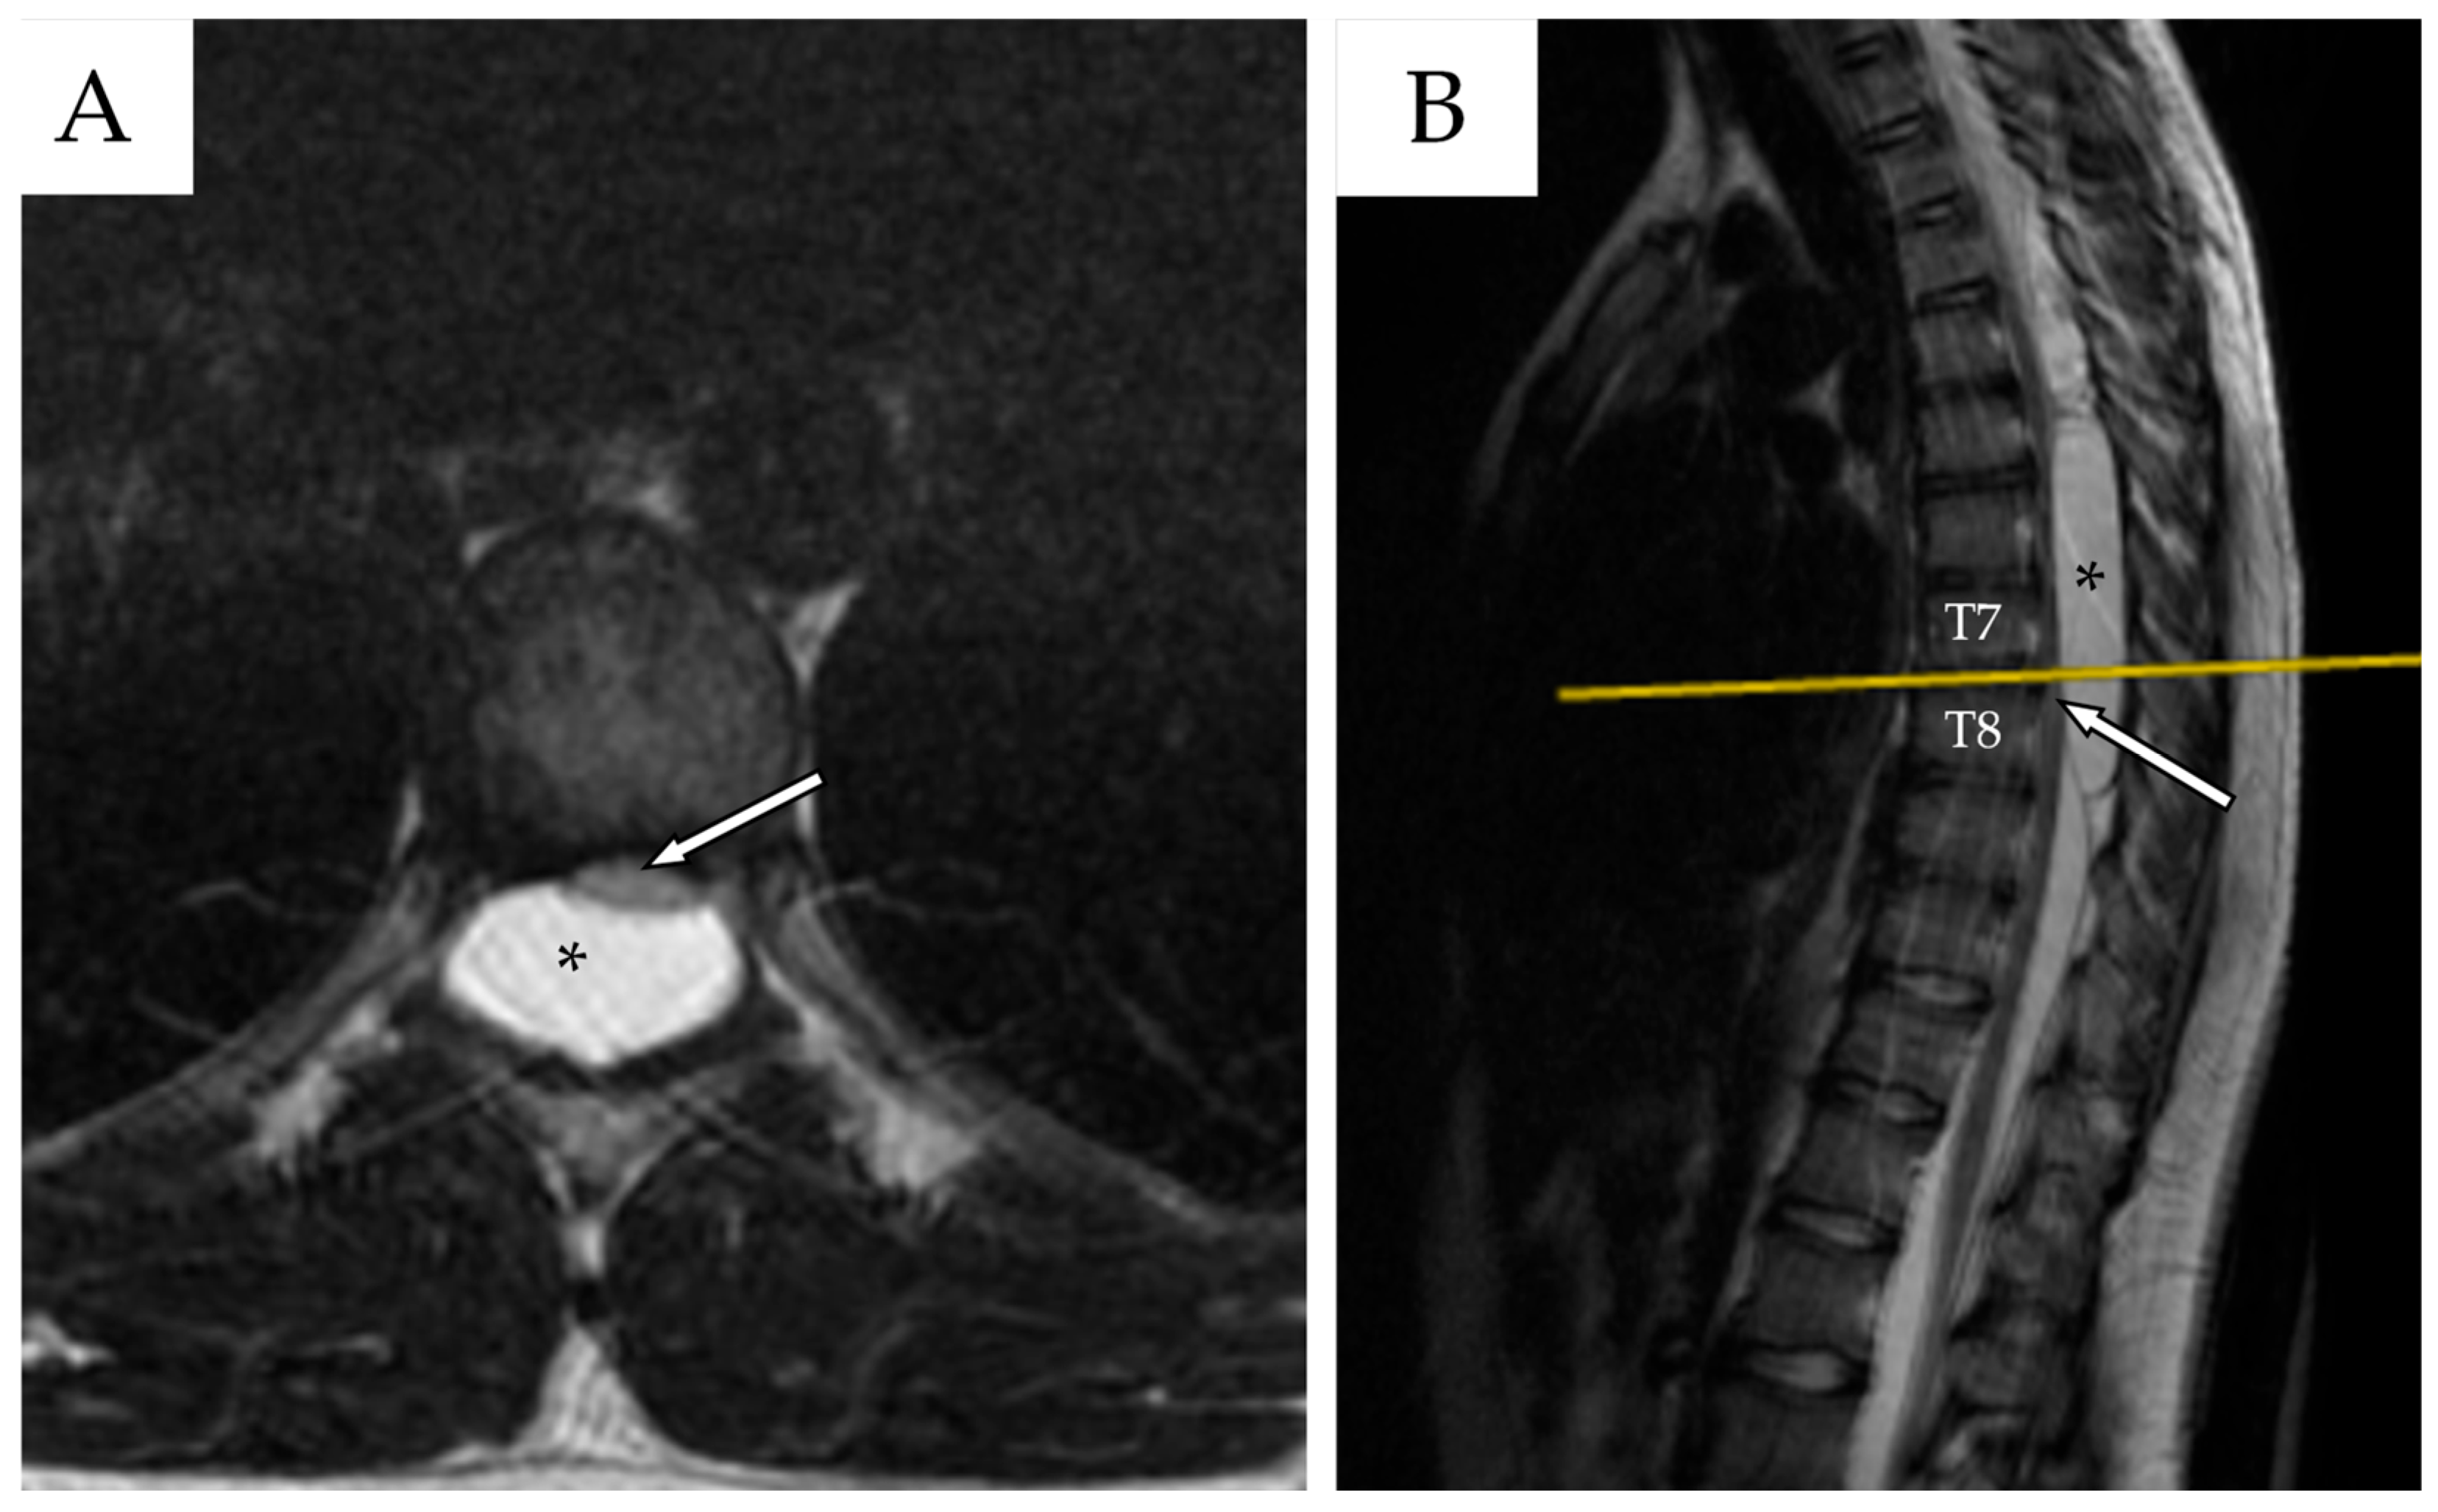

2.1. First Admission

2.2. First Follow-Up

2.3. Second Admission

2.4. Second Follow-Up